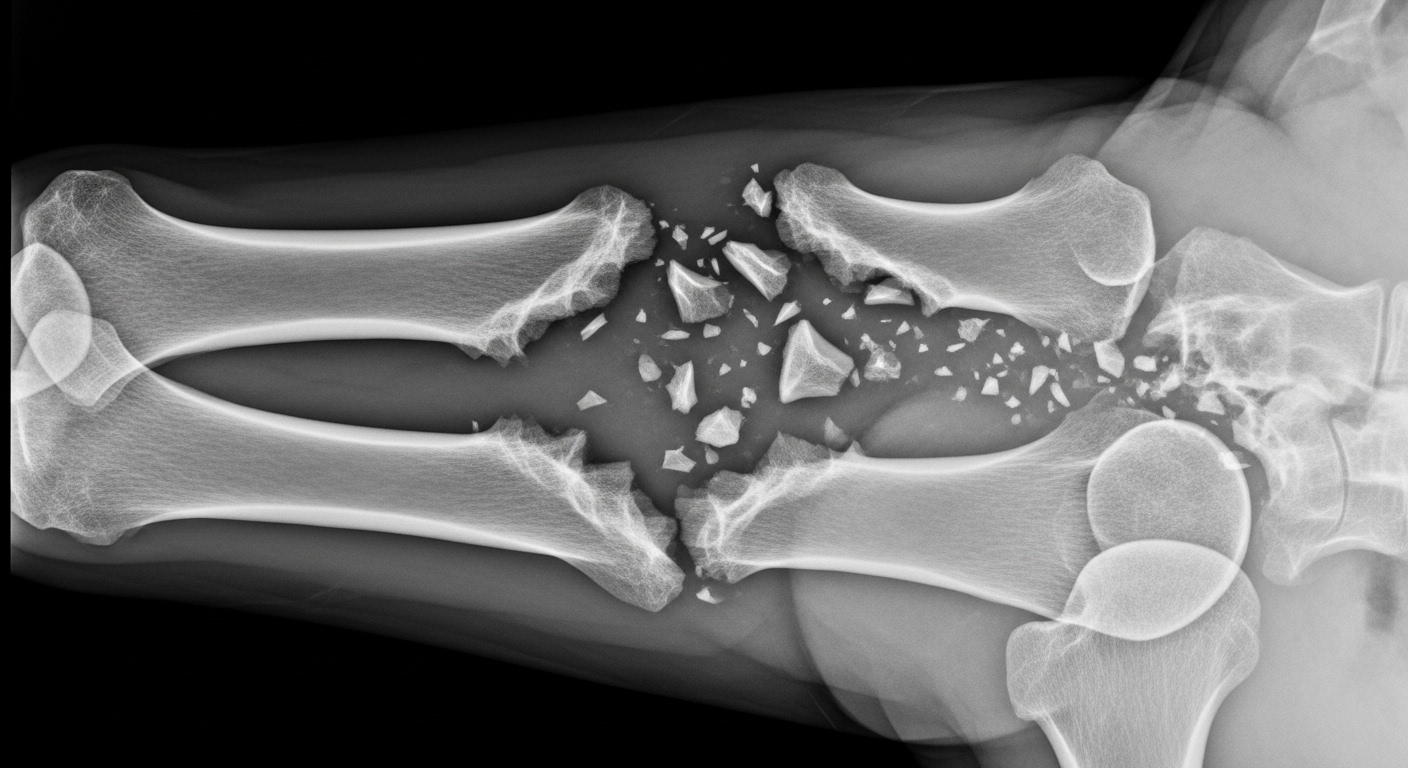

Le casse-tête des fractures complexes

Normalement, l’os est un champion de l’auto-réparation. Mais face à une fracture trop large, ou après l’ablation d’une tumeur, le corps a parfois besoin d’un coup de pouce. Les solutions actuelles ont leurs limites. Les greffes de donneurs ? Précieuses, mais rares et non sans risque de rejet. Les implants métalliques ou en polymères ? Ils comblent le vide, mais ne s’intègrent pas toujours parfaitement, ce qui peut fragiliser la reconstruction sur le long terme.

La théorie est séduisante, mais qu’en est-il en pratique ? L’équipe a testé son dispositif sur des lapins de Nouvelle-Zélande présentant des fractures sévères du fémur. Certains ont reçu l’implant bio-imprimé, les autres un ciment osseux classique. Douze semaines plus tard, le verdict était sans appel : les lapins du premier groupe montraient une guérison osseuse bien meilleure, avec une densité et une surface osseuse supérieures. Et surtout, aucune trace d’infection ou de nécrose n’a été observée.